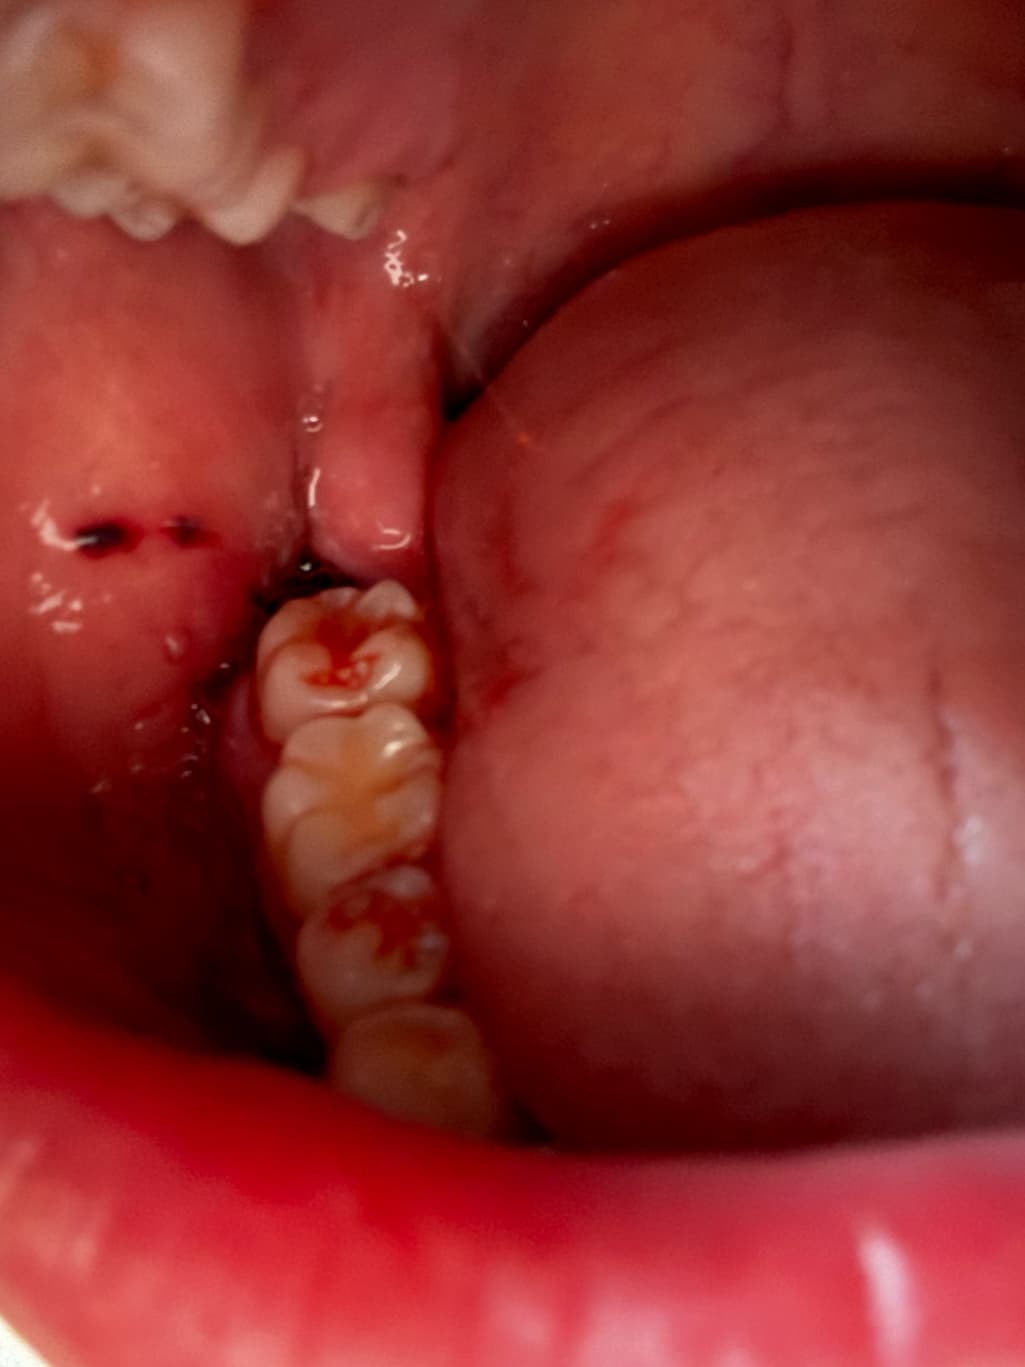

사랑니발치하고 현재 출혈이 멈춘 상태인가요?

오후2시쯤 뽑고 거즈물고 병원가서 5시쯤 거즈새로갈고 꾹물다가 오후8시쯤 땠어요.

침이 많이나와서 자주삼키는데 피는 고일정도로는 흐르진않는거같고 발치한부분잇몸으로 조금 흘러멈춘정도로 나온거같아요. 지혈된건가요???

사랑니발치하고 현재 출혈이 멈춘 상태인가요? -> 네 출혈이 심하지 않아보입니다 너무 걱정마세요

사진으로 봤을 경우에는 아직 출혈이 되고 있는 것으로 보입니다. 사랑니를 발치한 부위가 자극되지 않도록 하시고 거즈를 더 물고 있는 것이 좋을 것으로 생각됩니다

지혈은, 된 것이 맞으며 어느정도. 피가 새어나오는 것은 며칠 정도는 더 지속될 것 입니다.